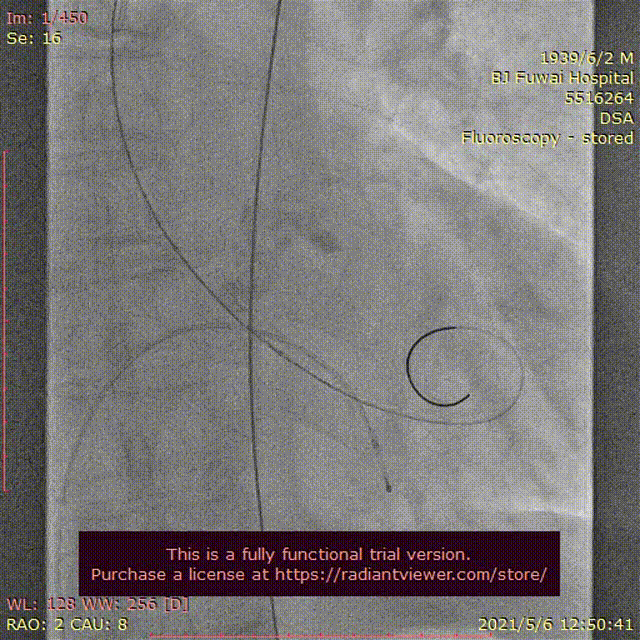

图3患者经导管主动脉瓣置换术及围术期操作

A:主动脉根部造影;B:23 mm球囊预扩张;C:26型号VenusA瓣膜植入;D:26型号VenusA“瓣中瓣”位置良好,少量瓣周漏;E和F:术前及术后经导管跨瓣压差;G:肘正中静脉留置针;H:患者全程清醒状态。